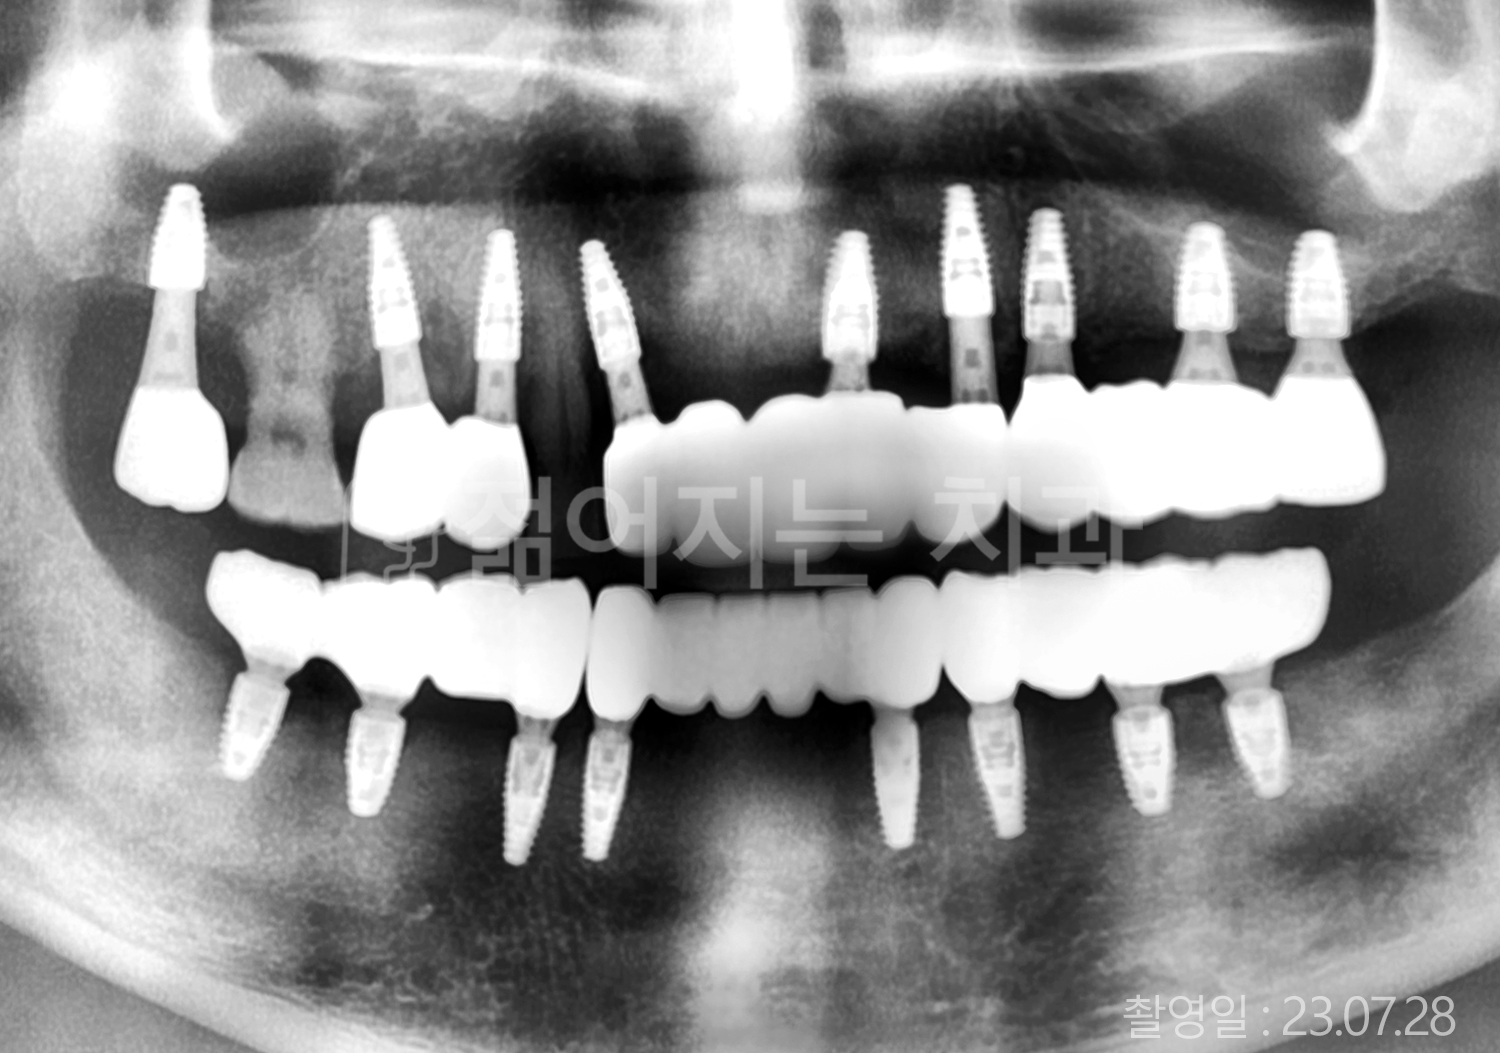

• 70대 고혈압, 고지혈증 전체치아 10개 이상 임플란트

• 60대 당뇨, 간염 전체치아 10개 이상 임플란트

• 80대 골다골증 전체치아 6개 이상 임플란트

• 70대 고혈압, 당뇨 전체치아 10개 이상 임플란트

• 60대 간 질환 전체치아 10개 이상 임플란트

• 60대 전체치아 10개 이상 임플란트

• 70대 전체치아 10개 이상 임플란트

• 50대 전체치아 10개 이상 임플란트

• 60대 고혈압, 고지혈증 전체치아 10개 이상 임플란트

• 40대 고지혈증, 뇌혈관 질환 전체치아 10개 이상 임플란트